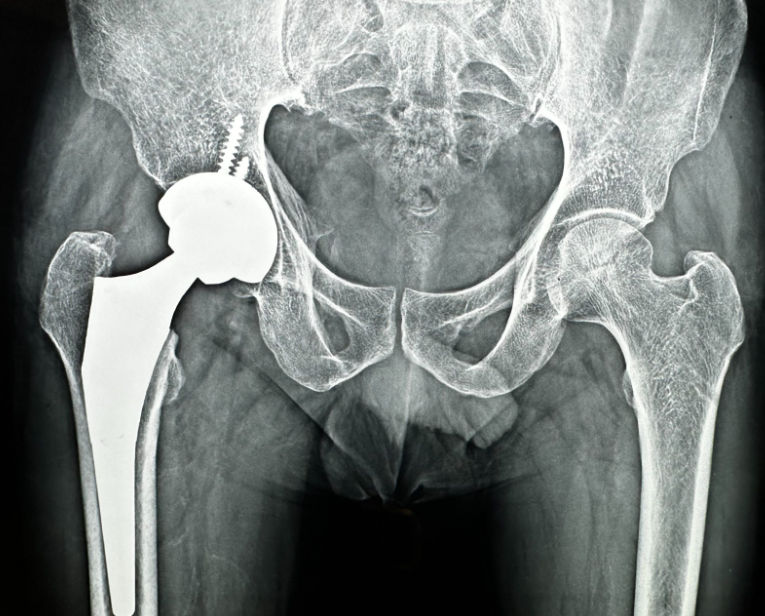

Is hip pain affecting how you sit, walk, or sleep? When conservative treatments stop providing relief, a hip replacement can restore your mobility and peace of mind. At Phoenix Orthopedic Superspecialty Hospital in Nagpur, skilled orthopedic surgeons perform precise, minimally invasive hip replacements designed to help patients move naturally and pain-free again.

The procedure replaces the damaged hip joint with an artificial implant that mimics the smooth movement of a healthy joint. Modern techniques ensure quicker recovery, reduced pain, and long-lasting results. With proper rehabilitation, patients can return to their daily activities and enjoy improved balance and comfort.

Living with chronic hip pain can lead to stiffness and decreased activity over time. Don’t wait for the condition to worsen. Visit a trusted orthopedic team in Nagpur and take your first confident step toward freedom from hip discomfort.